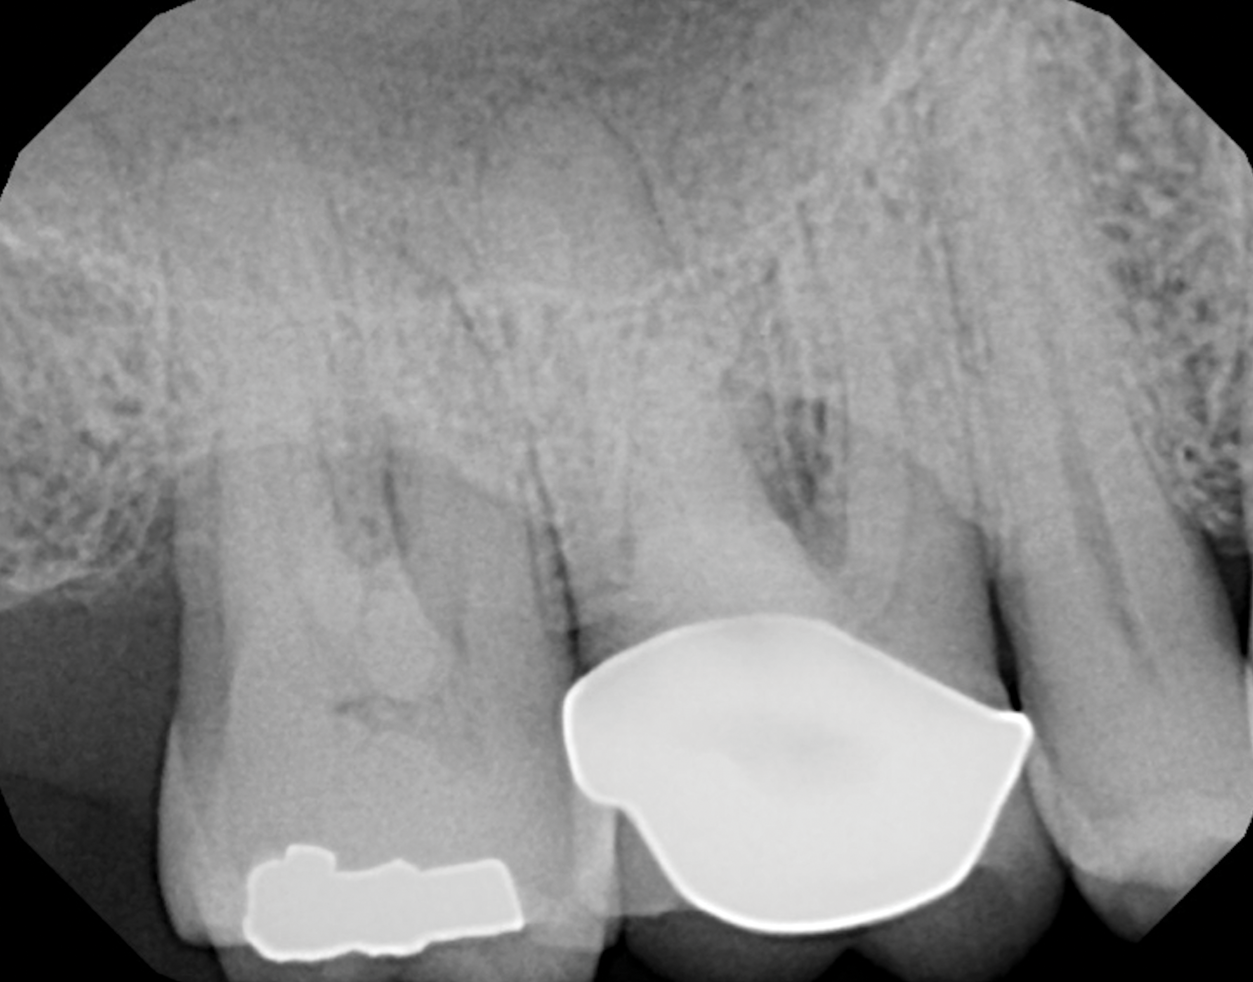

Fig 8. Periapical radiograph of the maxillary right first molar (identified as the most periodontally involved molar that was planned to be maintained).

Figure 8

Periodontal examination revealed generalized BOP and PDs up to 9 mm in the maxillary and mandibular molars with multiple furcations in each molar (Figure 2 through Figure 7). He presented with class I mobility in many posterior teeth and class II mobility in teeth Nos. 3 and 9 (maxillary right first molar and maxillary left central incisor, respectively). The periodontist decided to score tooth No. 3 for the PRS, as this was the most periodontally involved molar that was planned to be treated and maintained (Figure 2 and Figure 8). This tooth (maxillary right first molar = score 1) presented with probing depths of 7 mm (score 1); three total furcation invasions (score 3) (mesial [degree II furcation], buccal [degree I furcation], and distal [degree II furcation]); and a class II mobility (score 2). The total PRS for tooth No. 3 was 8, representing a "guarded" prognosis. Based on this score, the likelihood of not losing any teeth to periodontal disease for 15 years was 81%, and for 30 years the likelihood was just 56% (Figure 9).7